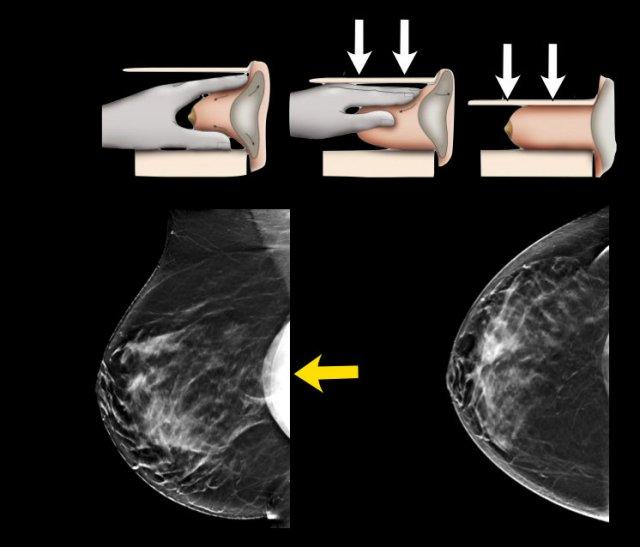

Chụp nhũ ảnh (Mammography)

Cùng một bệnh nhân trước và sau khi đặt túi ngực trước cơ ngực (prepectoral).

Đặc biệt, túi ngực đặt trước cơ ngực có thể làm giảm khả năng đánh giá trên nhũ ảnh.

Tuy nhiên, chụp nhũ ảnh thông thường và chụp cắt lớp tổng hợp 3D (3D tomosynthesis) vẫn có thể thực hiện tốt và thực tế có giá trị tiên đoán dương tính (PPV) cao nhất trong việc phát hiện silicon ngoài bao xơ.

Phương pháp này cũng giúp phát hiện khách quan các thay đổi theo thời gian, hiển thị các vôi hóa, có thể thấy bóng mờ dịch xung quanh và tất nhiên bổ sung các phát hiện quan trọng trong mô tuyến vú.

Kỹ thuật Eklund

Có thể thực hiện các tư thế chụp đặc biệt như tư thế Eklund.

Bằng cách đẩy túi ngực ra phía sau và kéo mô vú ra phía trước, có thể quan sát mô tuyến vú tốt hơn.

Chụp cắt lớp tổng hợp (Tomosynthesis)

Chụp cắt lớp tổng hợp có thể rất hữu ích như trong trường hợp này.

Người phụ nữ này có túi ngực chứa nước muối sinh lý và cho thấy hình ảnh van bơm dạng đĩa dẹt.

Có một khối, rõ hơn trên hình ảnh chụp cắt lớp tổng hợp (lát cắt 56 trong tổng số 73).

Đây là một khối có bờ tua gai.

Giải phẫu bệnh: ung thư tiểu thùy xâm nhập độ 2 và ung thư tiểu thùy tại chỗ (LCIS).